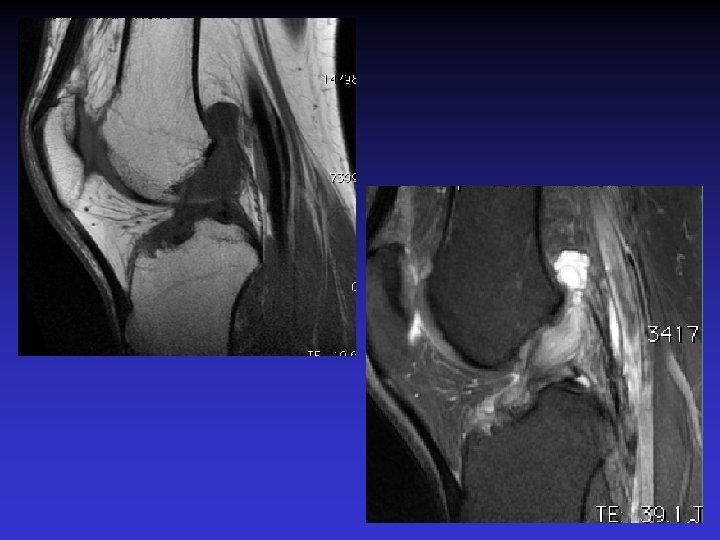

ASPECT IRM • • Hyposignal TI Hypersignal T 2 Pas de prise du contraste après Gado IV Continuité conservée du LCA+++ avec dilacération des fibres • Aspect en « tige de céleri »

GADO

ASSOCIATION A DES KYSTES MUCOIDES • Dans près de 50% des cas • Au contact ou à distance du LCA